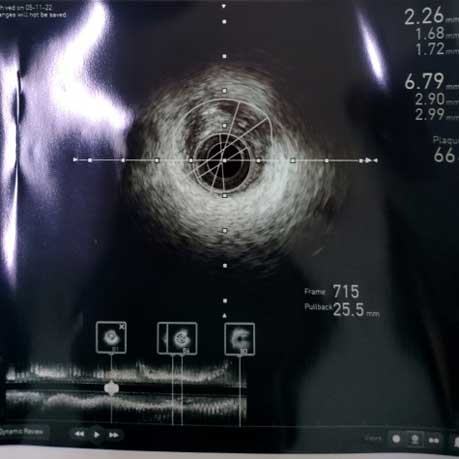

手术当天,在执行主任赵慧强的指导下,心内科介入团队根据患者2019年冠脉造影结果,应用血管内超声依次对冠状动脉的三支血管进行了无造影剂的检查,结果发现右冠近段和回旋支狭窄非常严重,右冠近段仅为2.26mm²,回旋支为1.9mm²(正常血管在3mm²以上),在血管内超声指导下依次完成对两个靶血管的介入治疗:预扩张——再次血管内超声评价残余狭窄——药物球囊扩张——血管内超声评价最终效果,介入治疗结果满意。术后右冠最小面积由2.26mm2增加到3.51mm2,回旋支最小面积由1.9mm2增加到3.34mm2,改善了心肌供血,缓解了症状。整个检查和治疗全程实现了“零”造影剂,避免了出现造影剂过敏反应和休克的发生,同时更精确地判断了冠脉的病变,精准地指导了介入治疗,取得了理想的治疗效果。

右冠术前

(右冠术前、术后的IVUS图像,可见血管腔明显扩大)